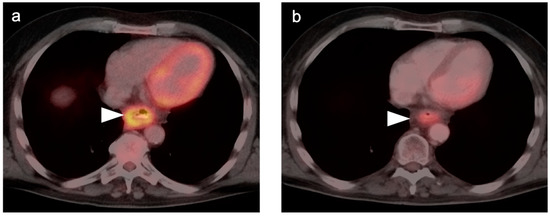

3. Gastrointestinal Stromal Tumor (GIST)